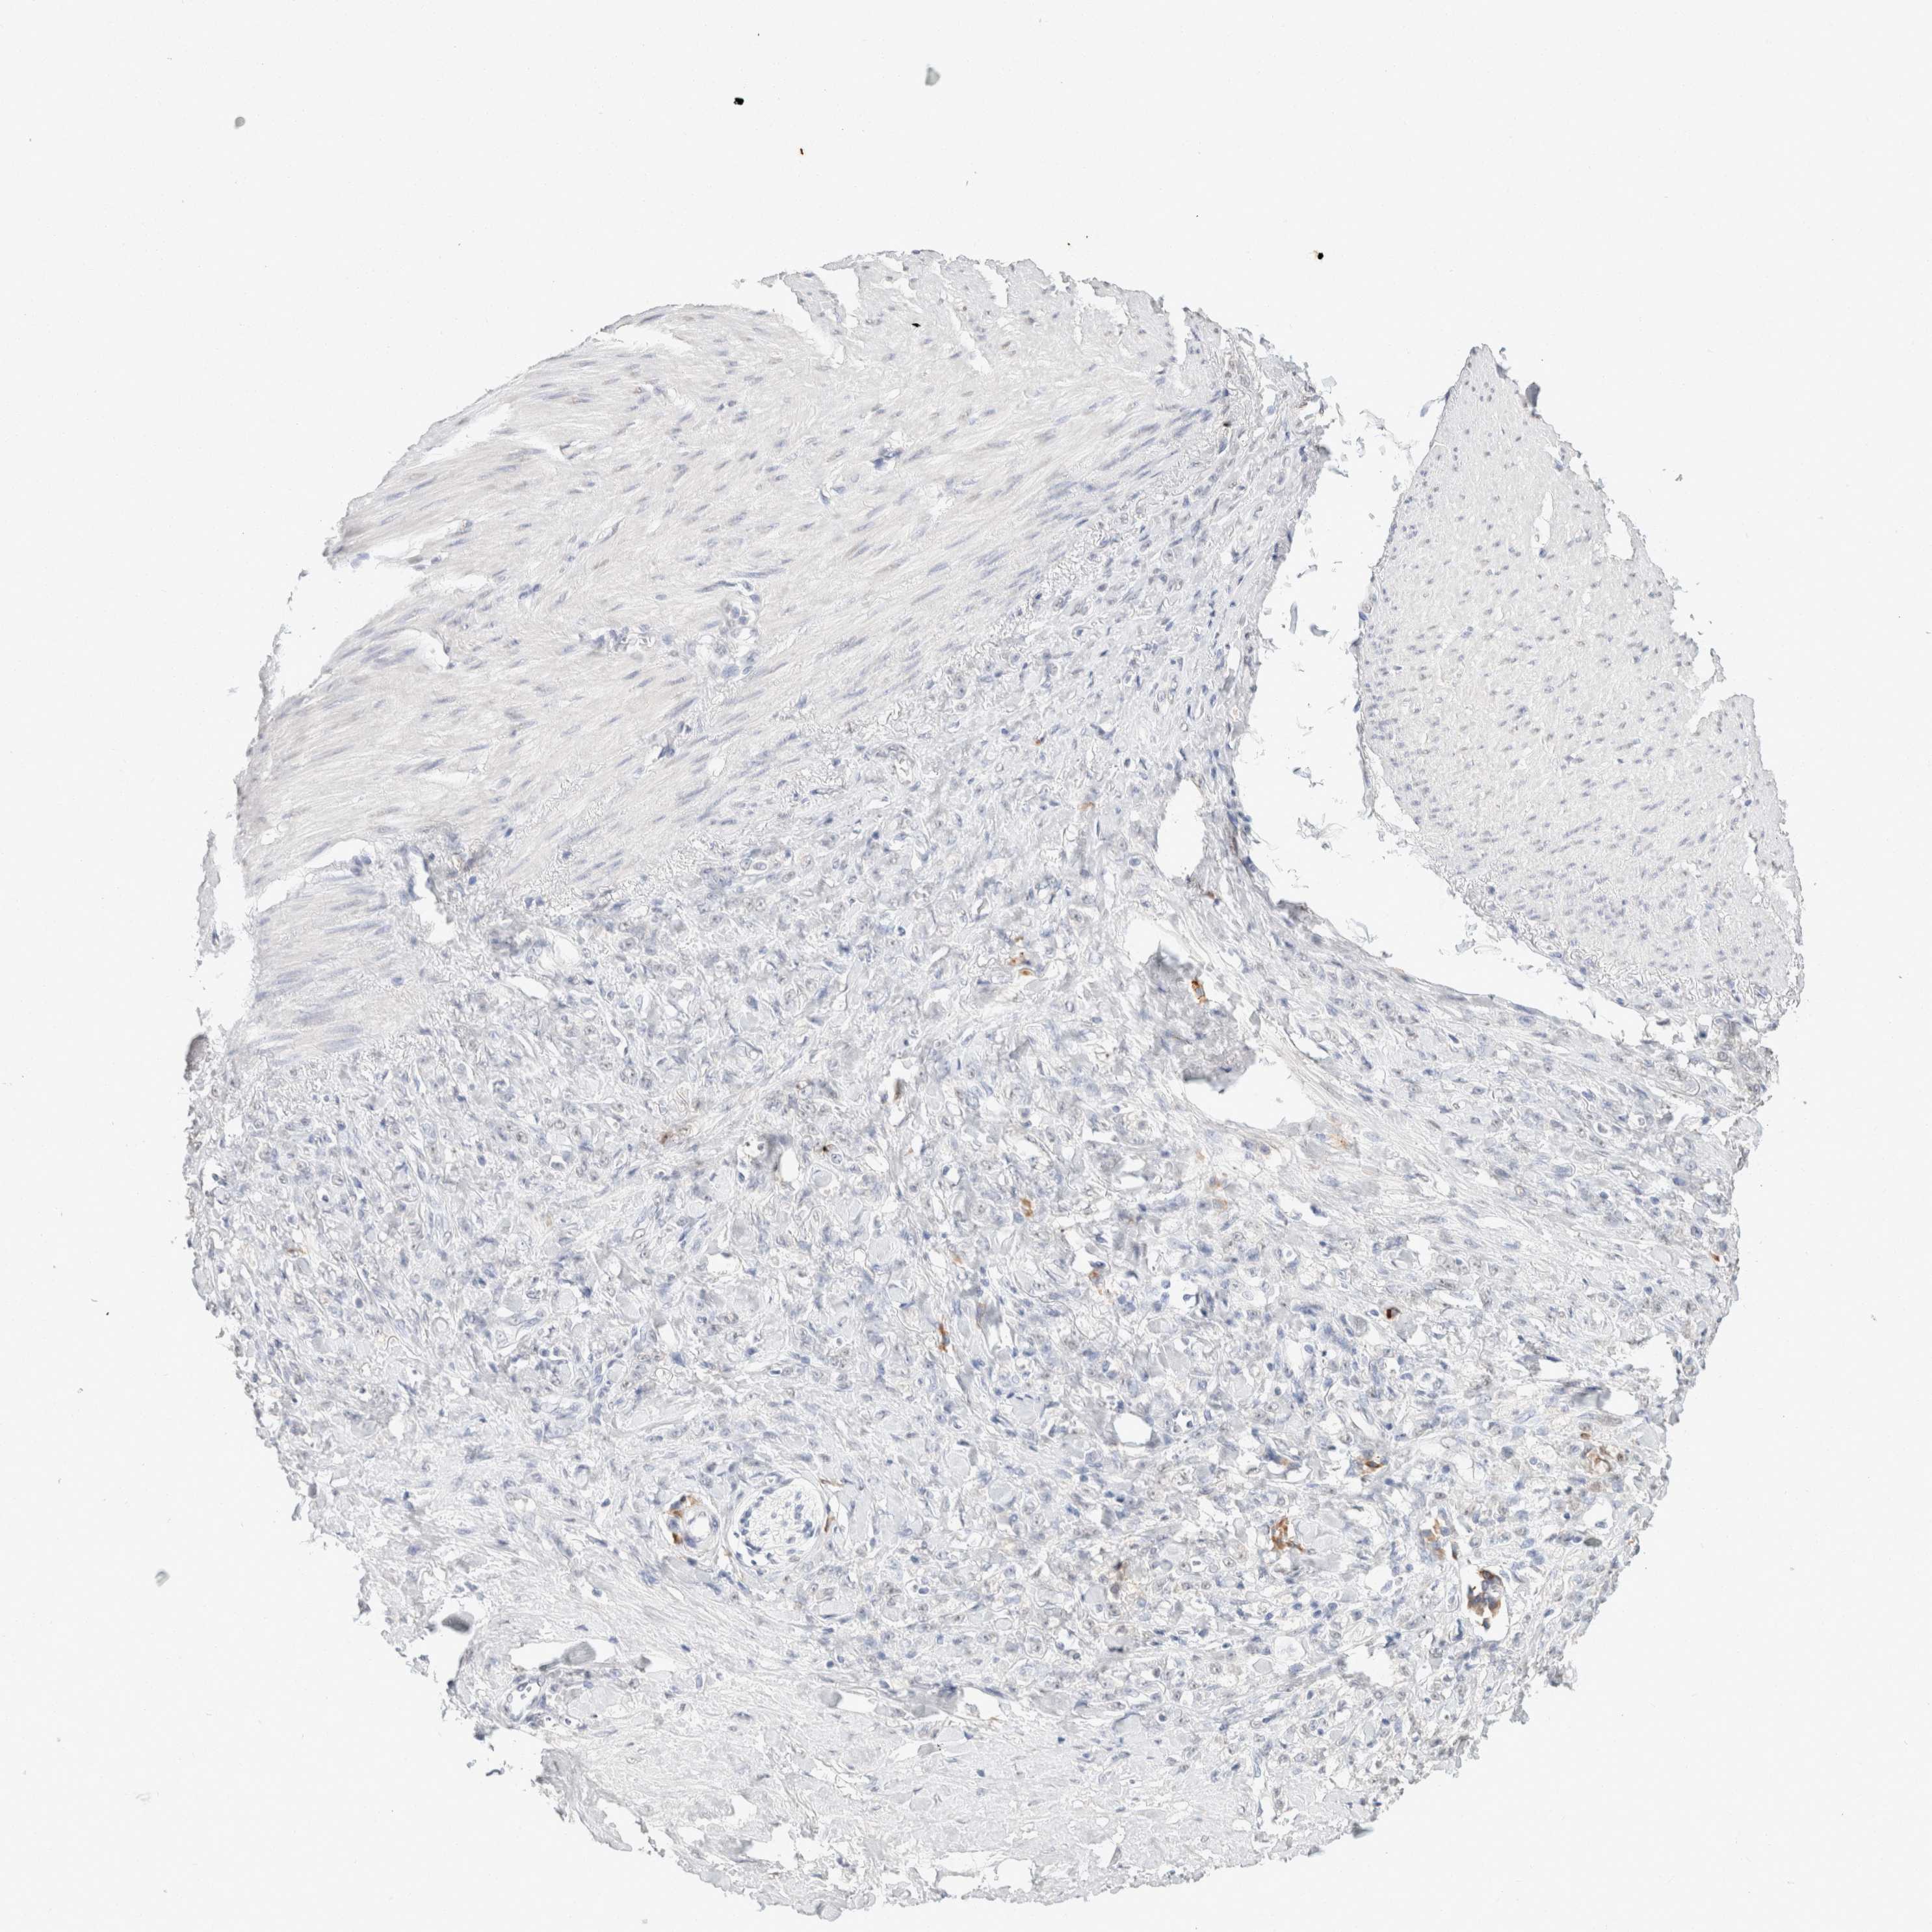

STOMACH CANCER - Protein expressioni

A mouse-over function shows sample information and annotation data. Click on an image to view it in a full screen mode. Samples can be filtered based on level of antibody staining by selecting one or several of the following categories: high, medium, low and not detected. The assay and annotation is described here.

Note that samples used for immunohistochemistry by the Human Protein Atlas do not correspond to samples in the TCGA dataset.

Antibody stainingi

Antibody staining in the annotated cell types in the current human tissue is reported as not detected, low, medium, or high, based on conventional immunohistochemistry profiling in selected tissues. This score is based on the combination of the staining intensity and fraction of stained cells.

Each image is clickable and will lead to virtual microscopy that enables deeper exploration of all samples and also displays staining intensity scores, fraction scores and subcellular localization as well as patient and tissue information for each sample.

Antibody HPA050092

Antibody CAB025368

Staining

High

Medium

Low

Not detected

Intensity

Strong

Moderate

Weak

Negative

Quantity

>75%

75%-25%

<25%

None

Location

Nuclear

Cytoplasmic/membranous

Cytoplasmic/membranous,nuclear

Adenocarcinoma, NOS

Adenocarcinoma, High grade